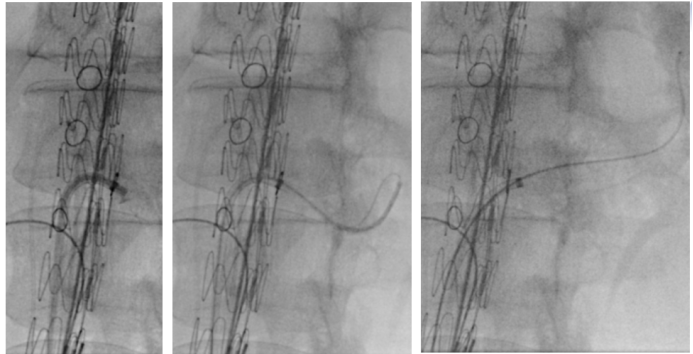

★ Case3:术中束径丢失,如何处理补救?男,72岁,胸腹主动脉瘤。

在一例胸腹主动脉瘤手术中,发生了罕见的“束径丢失”(束径导丝意外脱出),导致支架提前贴壁。面对危机,团队并未慌乱,而是迅速采取补救措施:

立即建立生命线: 从上肢紧急穿刺置入6F鞘,优先超选并保护SMA。

逆向思维,化险为夷: 在SMA这条“生命线”保障下,从容地从股动脉重新尝试超选其他分支,最终成功完成手术,避免了开腹手术。